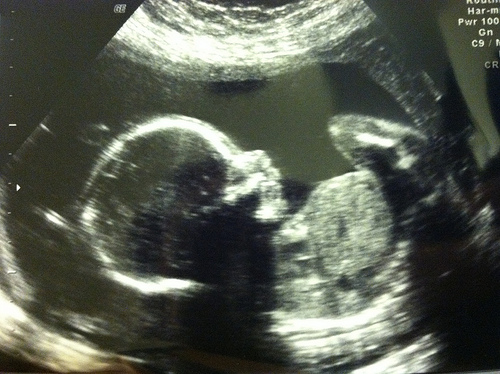

Let's start the Saturday Seeds this week with a pregnancy update. We are having another boy!! Just what I was hoping, but not what I was feeling. So, pretty surprised and VERY excited! Now, to pick a name? We have ONE in mind, surprisingly. We knew we would be in trouble picking out names if this one was another boy, because Judah was the only name we could agree on last time. My little sister actually texted me a name idea a few days ago, and we both really like it! Who knows... we haven't quite decided on it yet. (And, we will keep it a secret until d-day!) 😉 But, if you have any name ideas, leave me a comment, please! I can use all the help I can get. We want strong meaning, doesn't have to be Biblical (although you might think otherwise because of our little Judah).

I'm now 20 weeks pregnant, no belly shot this week (didn't have a chance on a day that I looked somewhat decent). 🙂 But, I'm feeling good (besides some discomfort while sleeping) and the baby is moving...a lot. My 20-week ultrasound not only revealed the baby's gender, but also displayed a very big baby. He's already in the 86th percentile (didn't even know they did stats at this point??)! So, I think we have another big baby on our hands, and hopefully this means an earlier delivery date like I had with Judah (almost 2 weeks early). YAY!

According to my What to Expect app on my iPhone, the baby is measuring the size of a banana, except since my baby is big, maybe he's the size of a pineapple? haha! No stretch marks (yet), no swelling (yet), but I do have a pain in my right bottom cheek up to my lower back and down behind my thigh when I bend over to pick anything up. Grrrrr....